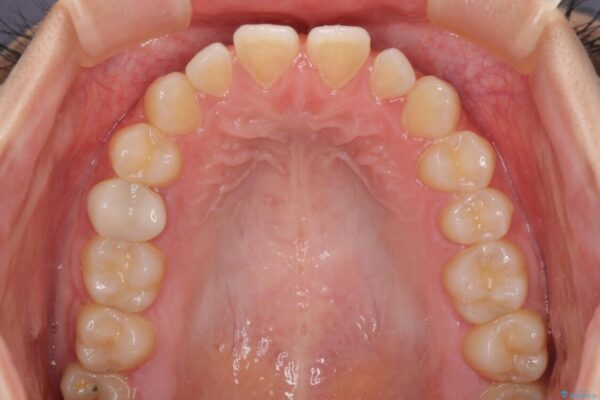

治療前

• 隙間だらけの歯列 インビザラインで改善 治療前画像

前歯の上下スペースと前歯の隙間を気にして来院された患者様です。

飲み込みや話をするときに舌を突出させる癖が強くあり、それが原因でスペースが空いていました。